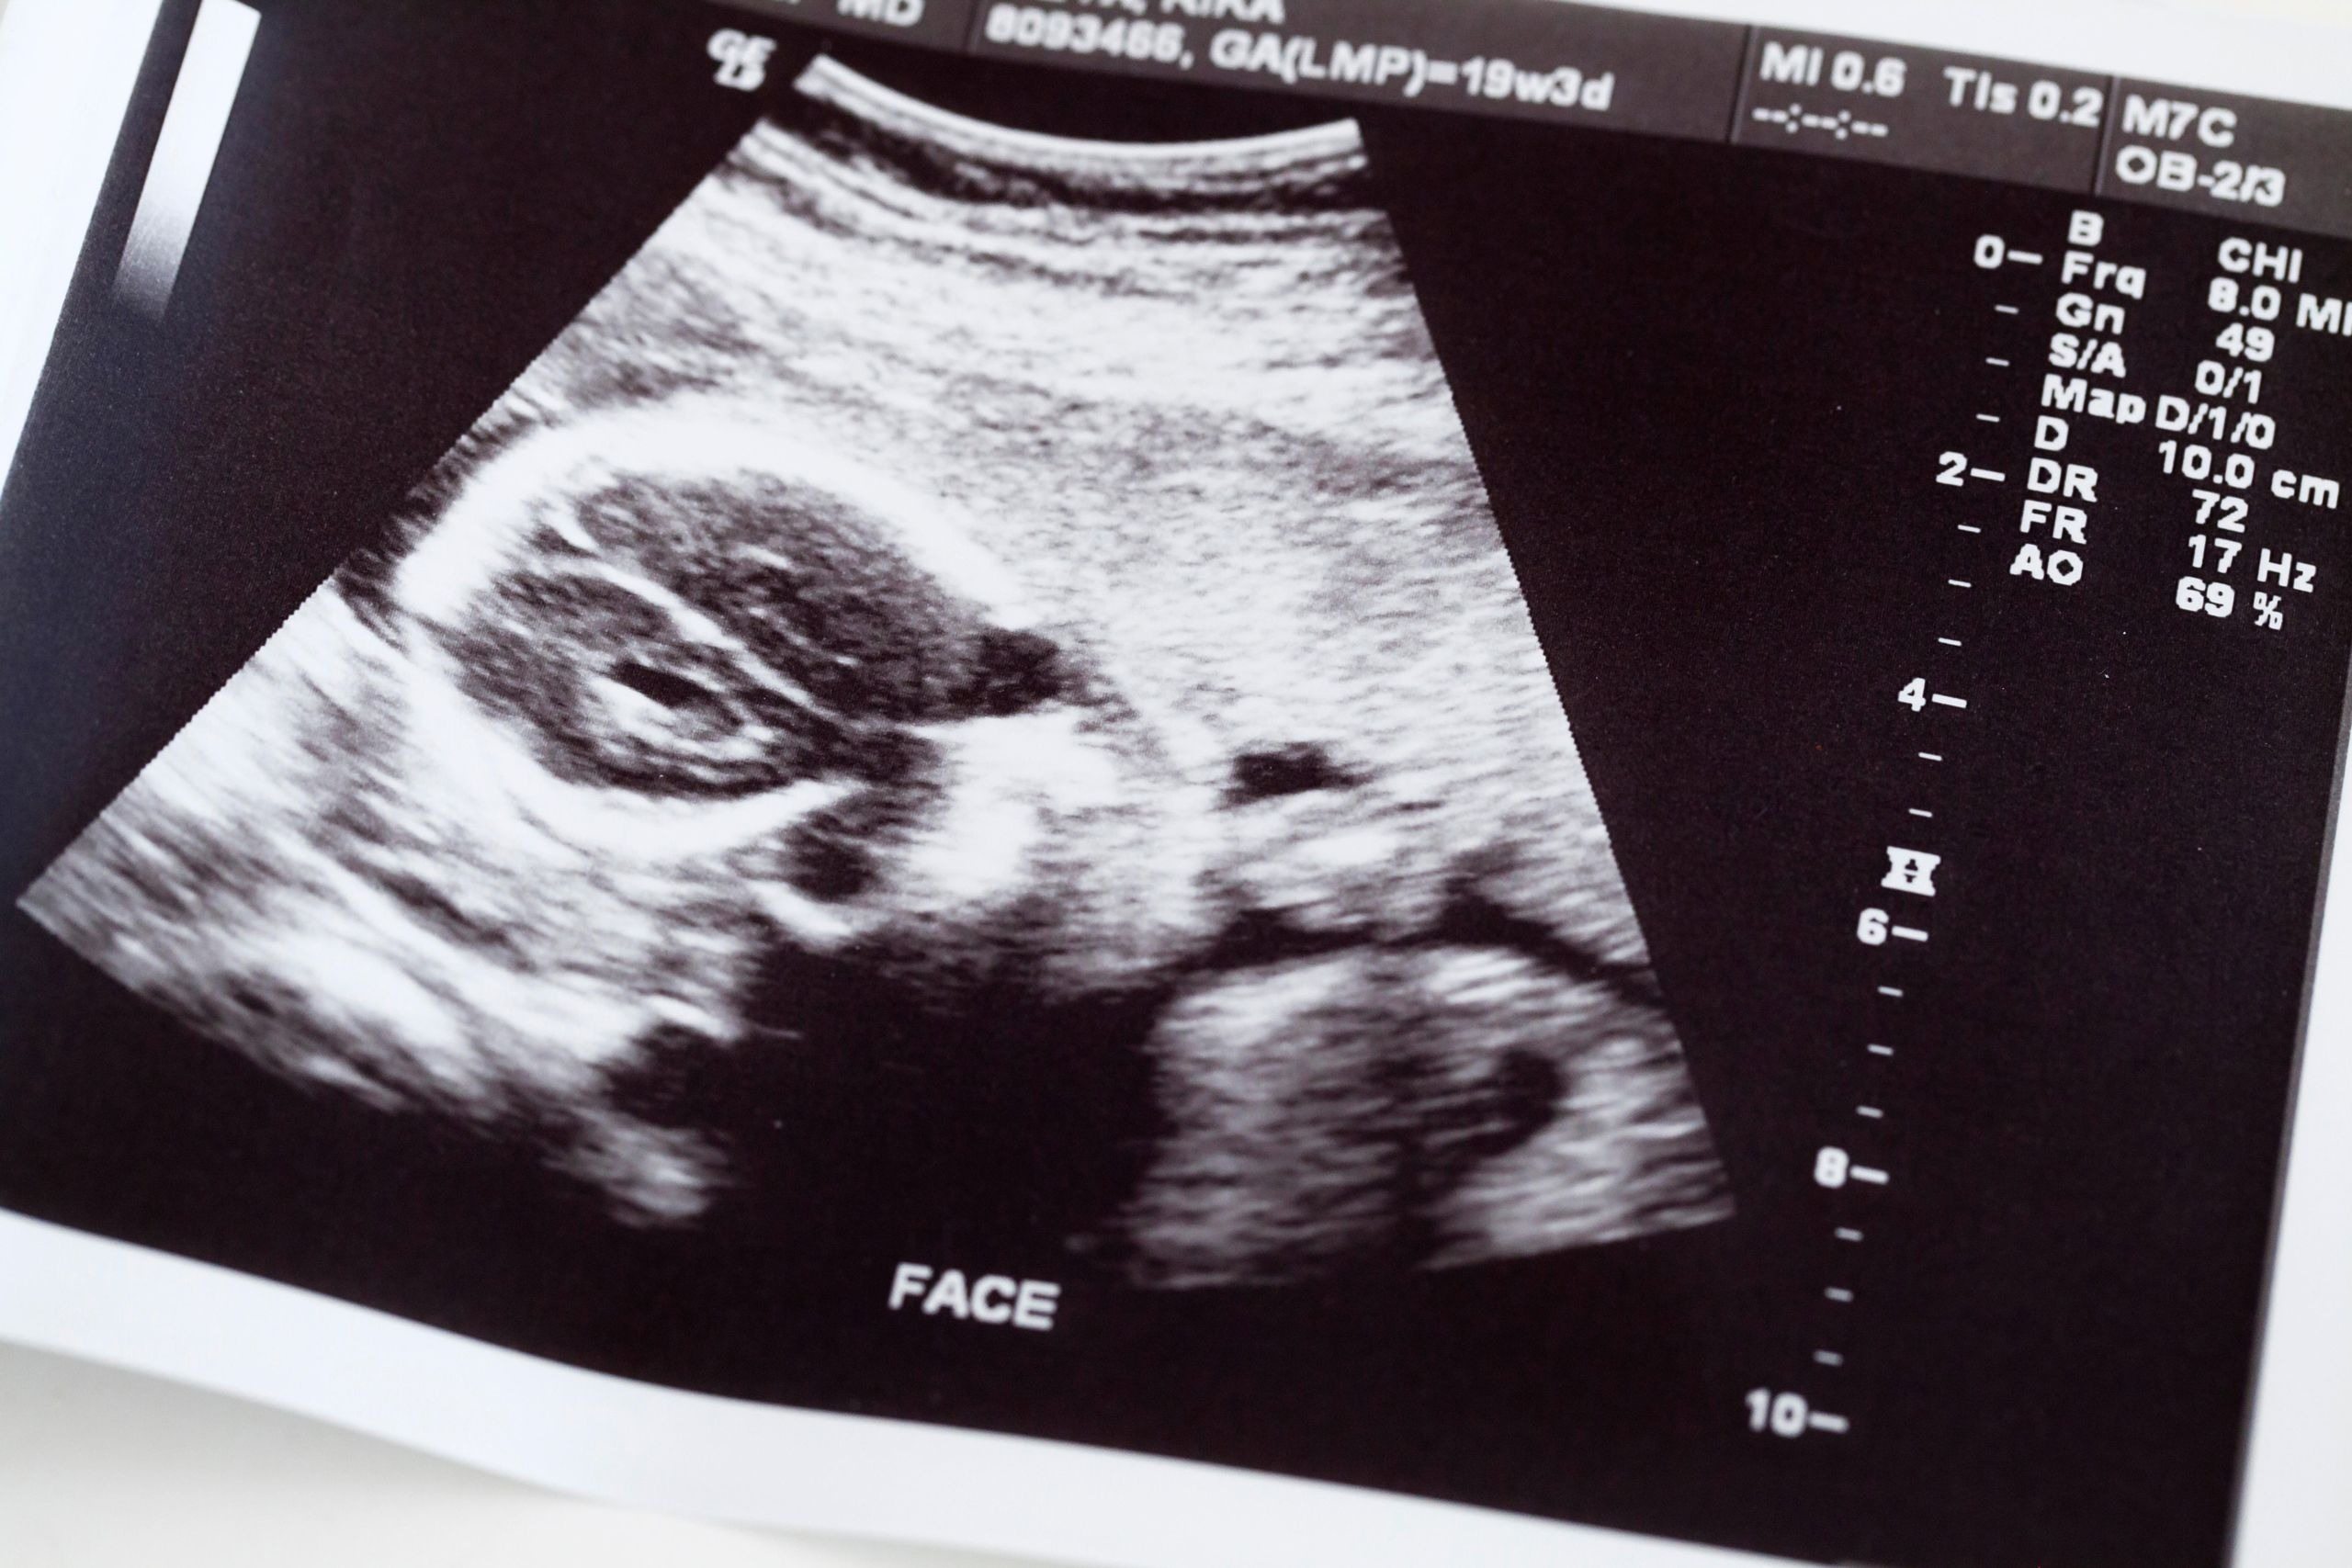

Sie dachte, ihre Schwangerschaft sei vorbei. Doch drei Wochen später entdeckten die Ärzte etwas Unfassbares

Lily war sich sicher, das Schlimmste überstanden zu haben.

Nach einer langen, kräftezehrenden Geburt kamen zwei Babys zur Welt – ein Sohn, Ezekiel, und eine Tochter, Zahra.